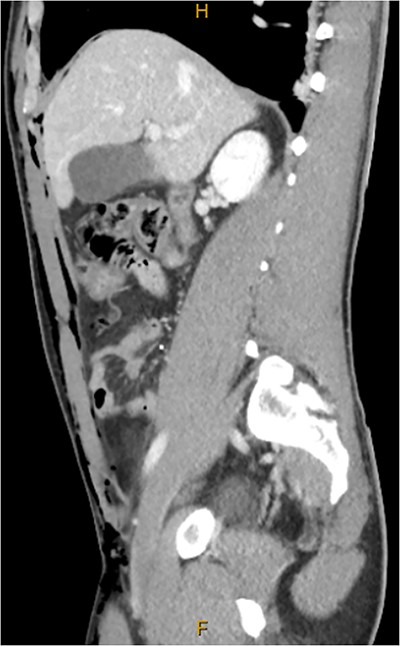

Following extubation, bilateral chest wall subcutaneous emphysema was noted extending to the neck. He also complained of central chest discomfort, without respiratory distress, oxygen desaturation or airway obstruction. Chest X-ray (CXR) revealed pneumomediastinum and surgical emphysema in the lateral chest walls bilaterally. Computed tomography (CT) of the chest, abdomen and pelvis demonstrated large volume subcutaneous emphysema bilaterally in the scrotum, abdominal and chest walls extending to the neck (see Figs 2–5). Gas was noted between the abdominal muscle layers, extraperitoneal and retroperitoneal spaces without pneumoperitoneum (see Figs 5–6). Moderate pneumomediastinum was prominent within the superior and antero-inferior mediastinum without evidence of tracheal or oesophageal injury and an associated small left pneumothorax was noted (see Figs 1–3).

CT abdomen and pelvis sagittal, abdominal wall subcutaneous emphysema with gas between muscle layers.